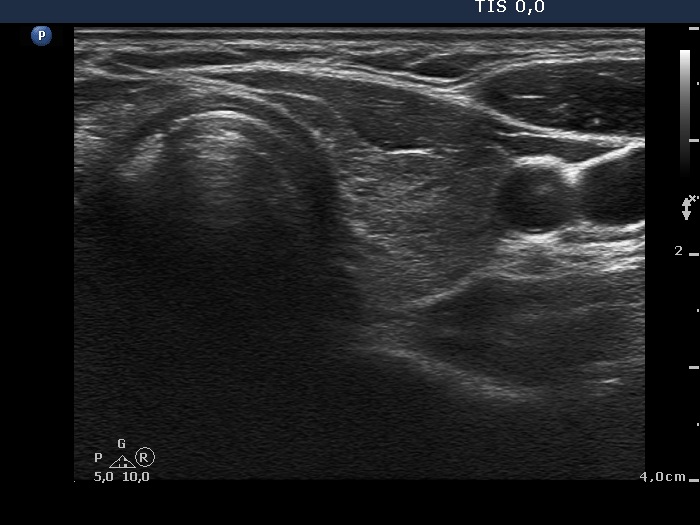

Ultrasonography: The thyroid was minimally-moderately hypoechogenic and presented fibrosis. There was a cystic lesion in the lower dorsal part of the right thyroid bed.